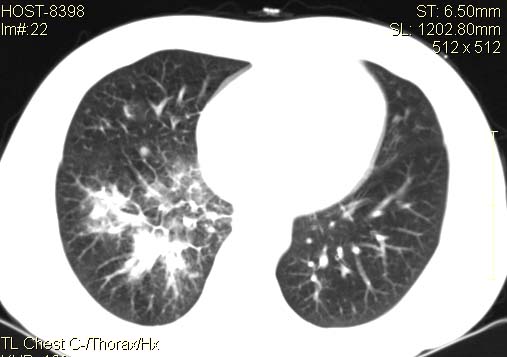

以下是引用qc80012345在2007-4-17 12:33:00的发言:[br]右肺下叶周围型肺癌伴肺门及纵隔内淋巴结转移;比较清楚。

以下是引用qingyuan在2007-4-17 14:19:00的发言:[br]右肺下叶外侧后段胸膜下区节结样病变、分叶、内可见空洞,壁厚薄不均,胸膜凹陷、肺门周围区纹理增粗、僵硬、并近似小结节样改变,肺门区软组织节结、纵膈淋巴结肿大,患者病史长、抗炎治疗无好转炎性改变基本排除,考虑:右肺下叶周围型肺癌伴纵膈及右肺门区淋巴结转移、肺内淋巴管受侵。